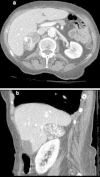

Presentation of case: A 78 year old woman was admitted after a fall. Abdominal computed tomography revealed a large right adrenal lesion with features suspicious for adrenal cortical carcinoma (5.4cm×3.3cm, unilateral, tumor calcifications, average Hounsfield units 55). The tumor was removed intact by a laparoscopic approach and pathology revealed a cavernous hemangioma of the adrenal gland.